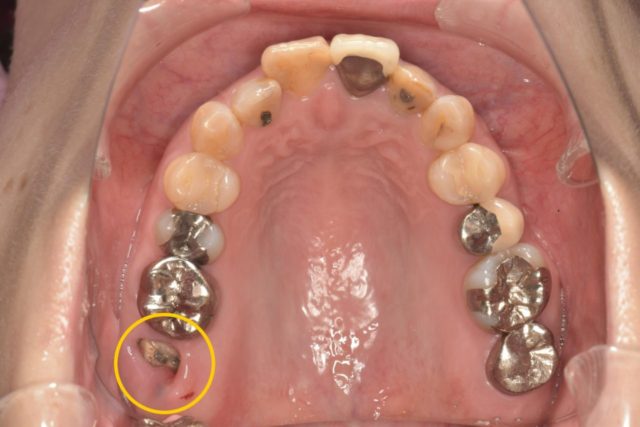

“右上の1番奥の歯を他院で抜歯と診断されだが残したい”という主訴で来院されました。

検査診断の結果、この歯は抜歯でIPを行うことになりました。

今回のケースは歯に歯茎が乗ってきているので、歯茎を切って下げることで歯を出す処置(歯冠長延長術)が必要です。

しかし歯茎がかなり覆い被さってるので、フェルールを獲得するためには7mm歯茎を切って下げないといけないのですが、そうなると歯の根っこが露出してしまうため、保存不可能という診断です。